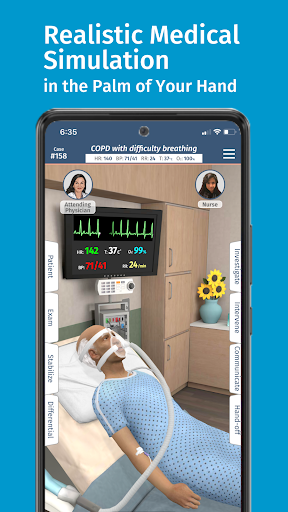

• Hơn 20 hình đại diện thực tế, bao gồm bệnh nhi và người lớn

Đào tạo mô phỏng theo yêu cầu của Full Code với các bệnh nhân ảo thực tế cho phép bạn thực hành các trường hợp phức tạp và nâng cao kỹ năng của mình bất cứ khi nào bạn có thời gian nghỉ ngơi, bất kể bạn ở đâu, trên các thiết bị bạn đã sở hữu. CẢI THIỆN SỰ TỰ TIN

Bệnh nhân và cảnh của chúng tôi trông và âm thanh chân thực hơn bao giờ hết.